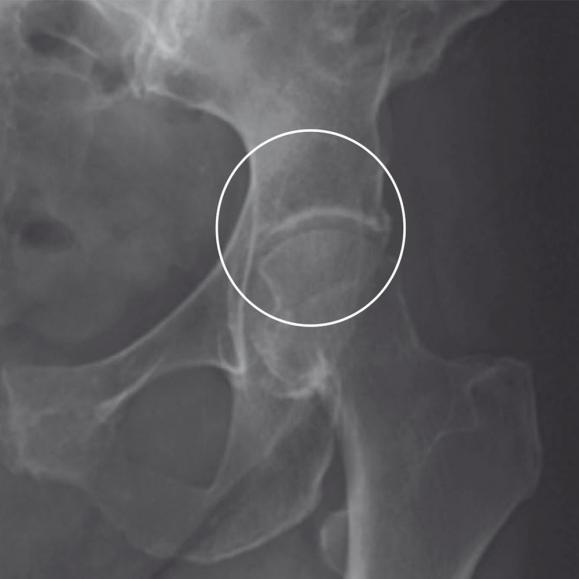

Entfernung des Hüftkopfes

Der erkrankte Hüftkopf wird vom Oberschenkelhals abgetrennt und entnommen.

Versorgung der Hüftpfanne

Nun wird die am Beckenknochen befindliche Hüftpfanne für die Implantation vorbereitet. Mit einer speziellen Fräse formt der Herr Petersen das Implantatbett. Dort wird dann die künstliche Hüftpfanne befestigt. Das geschieht meist mit Pressdruck, selten mit Zement oder verschraubt.

Versorgung des Oberschenkels

Der Markraum des Oberschenkelknochens wird mit Spezialraspeln aufgeraut und für die Aufnahme des Hüftschafts vorbereitet. Dieser wird in den Markraum des Oberschenkelknochens eingesetzt. Darauf wiederum wird dann der Hüftkopf aufgesetzt. Hier besteht die Wahl zwischen einer Einzementierung des Schaftes mit Knochenzement oder einem Einbringen, bei dem der Knochen langsam mit dem Schaft zusammenwächst. Je nach körperlichen Voraussetzungen kann für Sie die eine oder andere Variante angeraten sein. Beraten Sie sich mit Ihrem Facharzt Herrn Carsten Petersen, um die für Sie beste Befestigungsart zu ermitteln. Ist der Schaft in den Oberschenkelknochen eingebracht, wird der Hüftkopf auf seinem Hals befestigt.